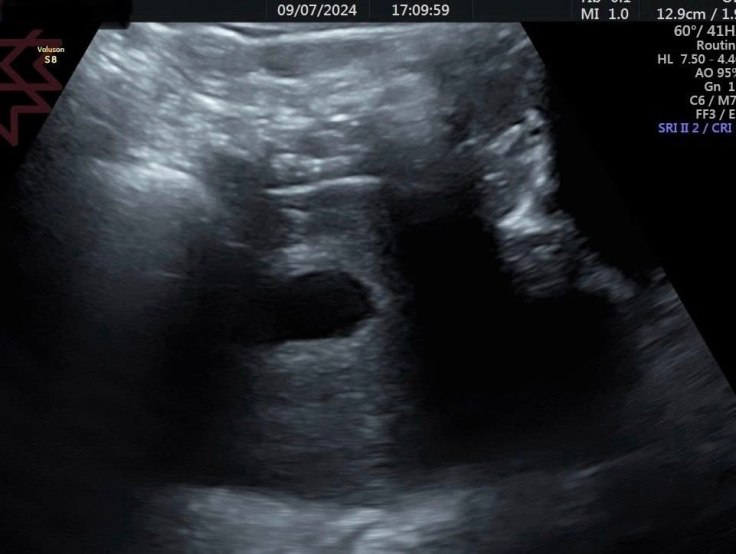

這兩張超音波圖片是同一個媽咪的

6+2週

前面一張是經腹部的超音波